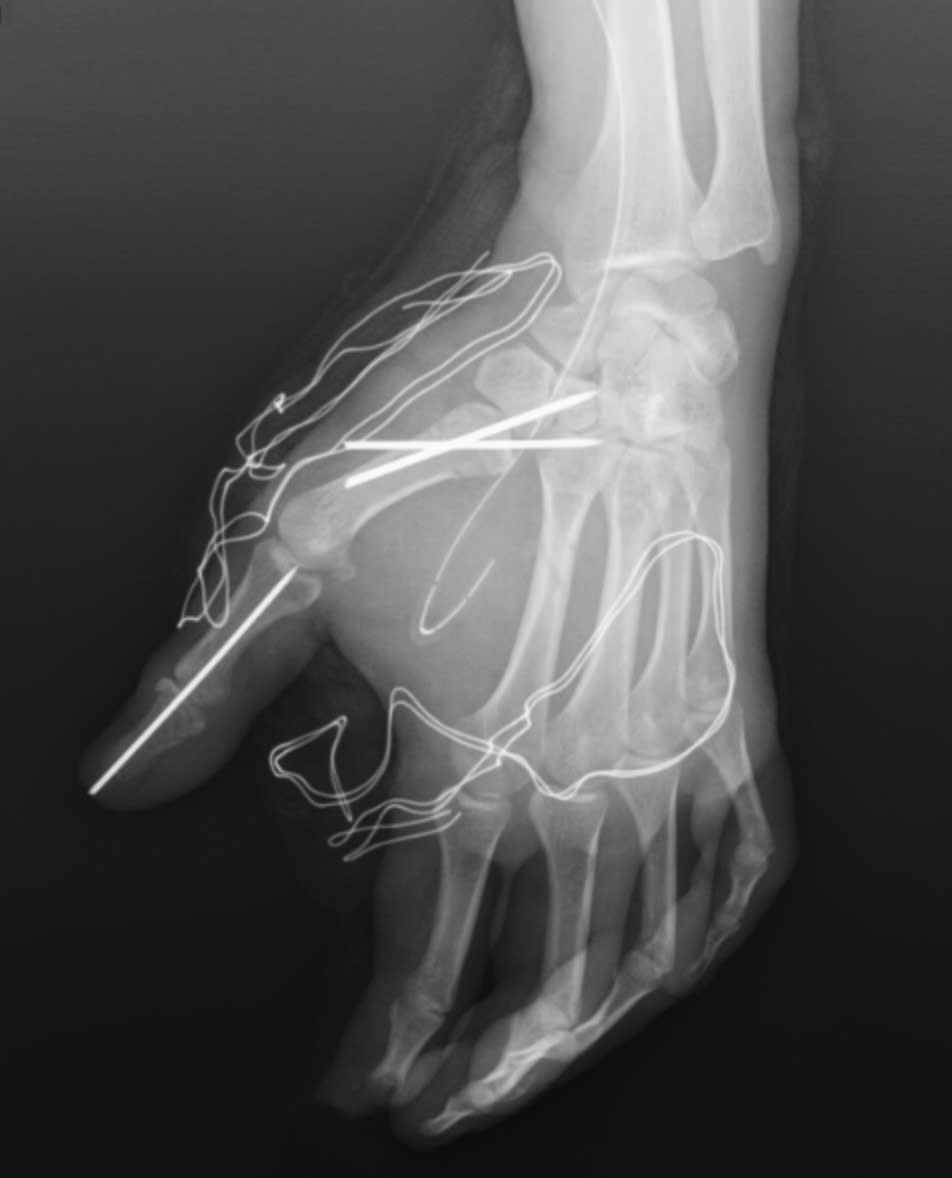

Ngay sau tai nạn, người bệnh được đưa đến cấp cứu tại Bệnh viện E. Khi thăm khám, bác sĩ ghi nhận người bệnh bị vết thương dập nát phức tạp bàn tay trái, chảy máu nhiều, nguy cơ tổn thương gân, mạch máu và thần kinh, có nhiều dị vật và mô hoại tử trong vết thương và nguy cơ mất chức năng bàn tay nếu không xử trí kịp thời.

Trong quá trình phẫu thuật, các bác sĩ khoa Phẫu thuật Chấn thương Chỉnh hình và Y học thể thao đã tiến hành cắt lọc tổ chức dập nát, lấy bỏ dị vật trên bàn tay của người bệnh. Đồng thời, vết thương được làm sạch, các cấu trúc gân, thần kinh và mạch máu còn lại được bảo tồn tối đa. Cuối cùng, các bác sĩ cố định xương gãy và khớp bị trật cho người bệnh.

Bàn tay nạn nhân bị dập nát sau tai nạn pháo nổ.